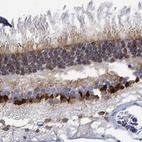

Immunohistochemical staining of human retina shows strong nuclear and cytoplasmic positivity in inner nuclear and ganglion cell layers.